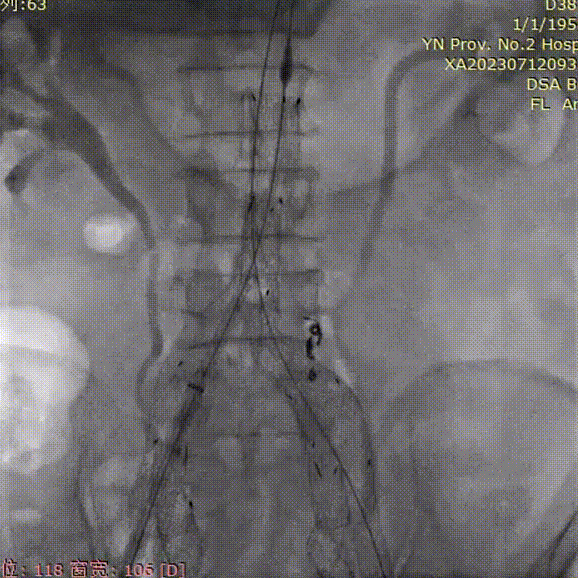

最后造影

支架锚定位置如预期,隔绝良好,无明显内漏;双侧髂内动脉血供得以保留,血流通畅。